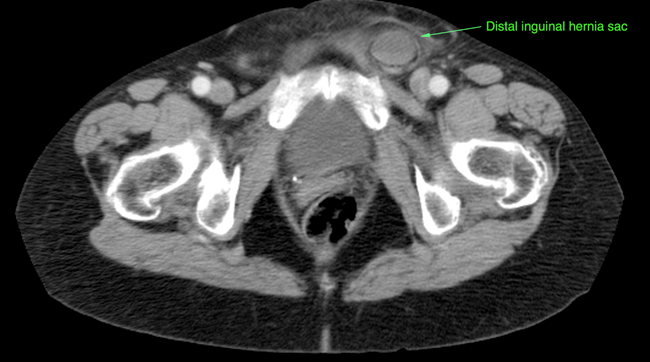

Incarcerated Inguinal Hernia